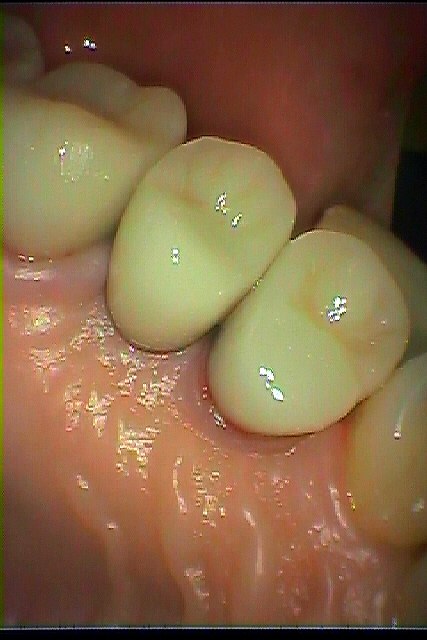

インプラントの最終補綴へ 埋入より3か月後になります|お知らせ |広島市安佐南区の歯科医院 インプラントの最終補綴へ 埋入より3か月後になります トップ お知らせ・ブログ お知らせ インプラントの最終補綴へ 埋入より3か月後になります インプラントの最終補綴へ 埋入より3か月後になります このように傷が治ります きれいに治っています カスタムアバットメントにて作成しています このように立ち上げています レントゲンにてもソーサライゼーションの起こりにくい埋入深さになります オールセラミックにて作成しています 抜歯窩にもドリリング時には足を取られ、上顎洞も持ち上げながら、 スペースが狭くなっていることもあり、5番は少し傾斜埋入となりました Web診療予約 初めての方へ 選ばれ続ける理由 院内設備について 歯が痛いしみる一般歯科 歯がぐらぐらする歯周病 健康な歯を保ちたい予防歯科 子供の虫歯予防をしたい小児歯科 銀歯をセラミックに審美歯科 白い歯を目指しませんか?ホワイトニング 矯正専門医がいるので安心矯正歯科 抜けた歯を補いたいインプラント・入れ歯 医院案内 スタッフ紹介 メリィハウス歯科クリニックオフィシャルホームページ ラベンダー歯科クリニックオフィシャルホームページ お知らせ・ブログ ホーム 診療科目 一般歯科 歯周病治療 予防治療 小児歯科 審美治療 ホワイトニング 矯正歯科 入れ歯・インプラント マウスピース矯正 初めての方へ 院長・スタッフ 設備紹介 医院案内・アクセス メニューを閉じる